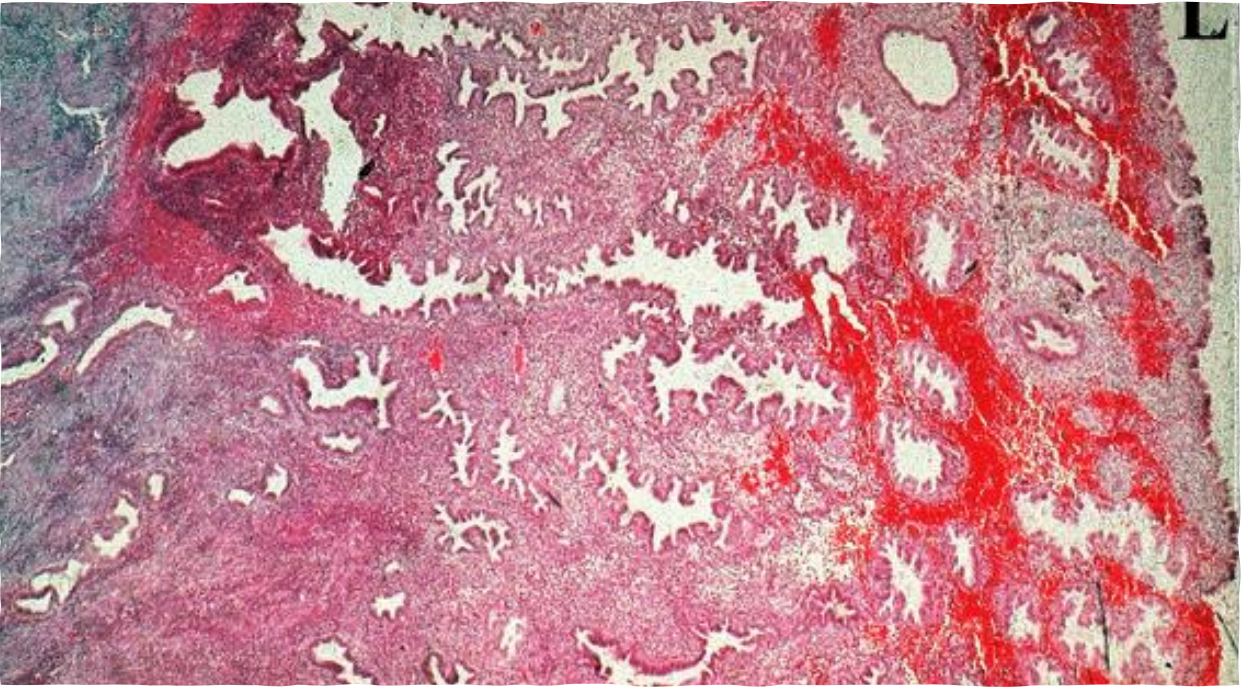

Prostate